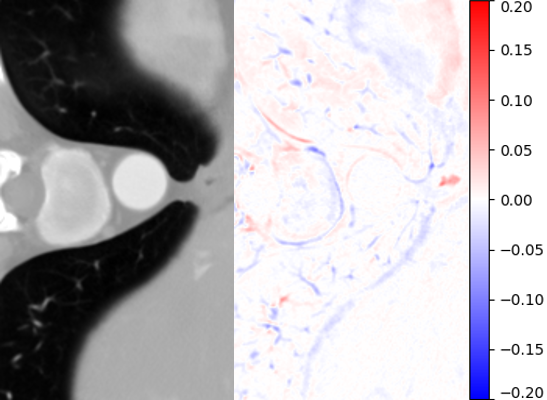

Figure 6: Visual comparisons of different methods against AMI. The difference maps are provided to the right of the results for better visualization. Images are best viewed when magnified.

1. A)

MDSR: Proposed by Lim et al. [17], MDSR can super-resolve images with multiple upsampling factors.

2. B)

RDN: The original RDN architecture, which allows for fixed upsampling factors.

3. C)

Meta-SR: Using the same RDN structure for feature learning, Meta-SR dynamically generates convolutional kernels based on Location Projection for the last stage.

Table 4 summarizes the performance of different implementations against AMI, evaluated on Isag(x,y,z)subscript𝐼𝑠𝑎𝑔𝑥𝑦𝑧I_{sag}(x,y,z), which we find to have better quantitative results than Icor(x,y,z)subscript𝐼𝑐𝑜𝑟𝑥𝑦𝑧I_{cor}(x,y,z) for all methods. For both rz=4subscript𝑟𝑧4r_{z}=4 and rz=6subscript𝑟𝑧6r_{z}=6, we found improvement in image quality from AMI over other methods, while Meta-SR and RDN have comparable performance. Despite the higher parameter number, MDSR ranked last due to using different substructures for different upsampling factors. For visual demonstration, we can see in Fig. 6 that AMI is able to recover the separation between the bones of the spine, while other methods lead to erroneous recovery where the bones are merged together. Compared to Meta-SR, AMI generates HW𝐻𝑊HW times less filter weights in its filter generation stage. With finite memory, this allows for GPUs to handle more slices in parallel, and achieve faster inference time per volume.

To examine the robustness of different methods, in addition to rz=4subscript𝑟𝑧4r_{z}=4 and rz=6subscript𝑟𝑧6r_{z}=6, we also tested the methods on rz=2subscript𝑟𝑧2r_{z}=2, which is not included in training. AMI and Meta-SR can dynamically adjust the upsampling factor by changing the input to the filter generation network. For 2D MDSR and 2D RDN, we use the rz=4subscript𝑟𝑧4r_{z}=4 version of the networks to over-upsample Irz=2x(y,z)subscriptsuperscript𝐼𝑥absentsubscript𝑟𝑧absent2𝑦𝑧I^{x}_{\downarrow r_{z}=2}(y,z) and Irz=2y(x,z)subscriptsuperscript𝐼𝑦absentsubscript𝑟𝑧absent2𝑥𝑧I^{y}_{\downarrow r_{z}=2}(x,z), and downsample the output by factor of two axially to obtain results. We observe significant degradation in Meta-SR’s performance as compared to other methods. Since Meta-SR’s input to its filter generation stage is dependent on the upsampling factor, an unseen upsampling factor can negatively affect the quality of the generated filters. In comparison, AMI does not explicitly include upsampling factor in its filter generation input, and performs robustly on the unseen upsampling factor.